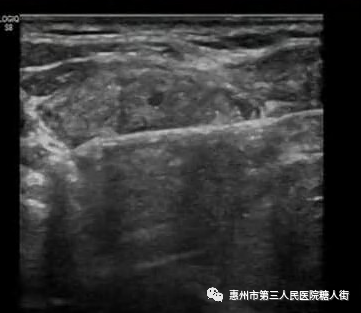

甲狀腺結(jié)節(jié)細(xì)針穿刺技術(shù)、甲狀腺結(jié)節(jié)熱消融術(shù)治療